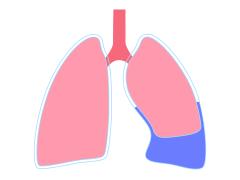

Thoracocentese: juiste indicatie en juiste plaats?